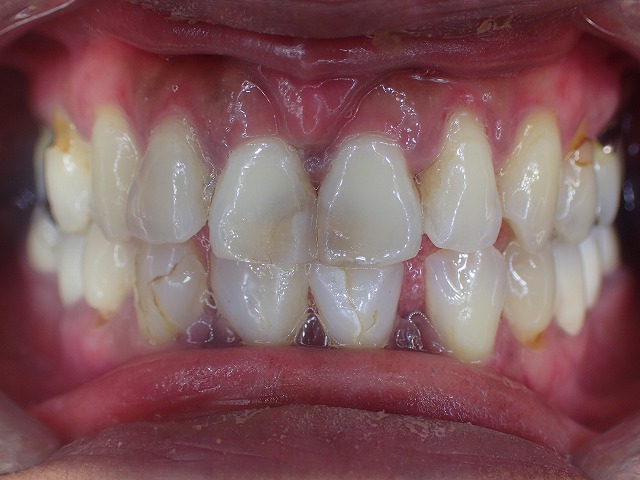

初診時画像 レジン充填 虫歯治療のあとが目立ちます レジン充填は劣化します

レジン充填が多数してあります。

この状態だと劣化して着色以外にも

大きく崩れてくるリスクがあります。

奥歯ないために、前歯で咬む癖があり

歯の先端から崩れ始めています。

下顎の前歯は2本欠損しています。